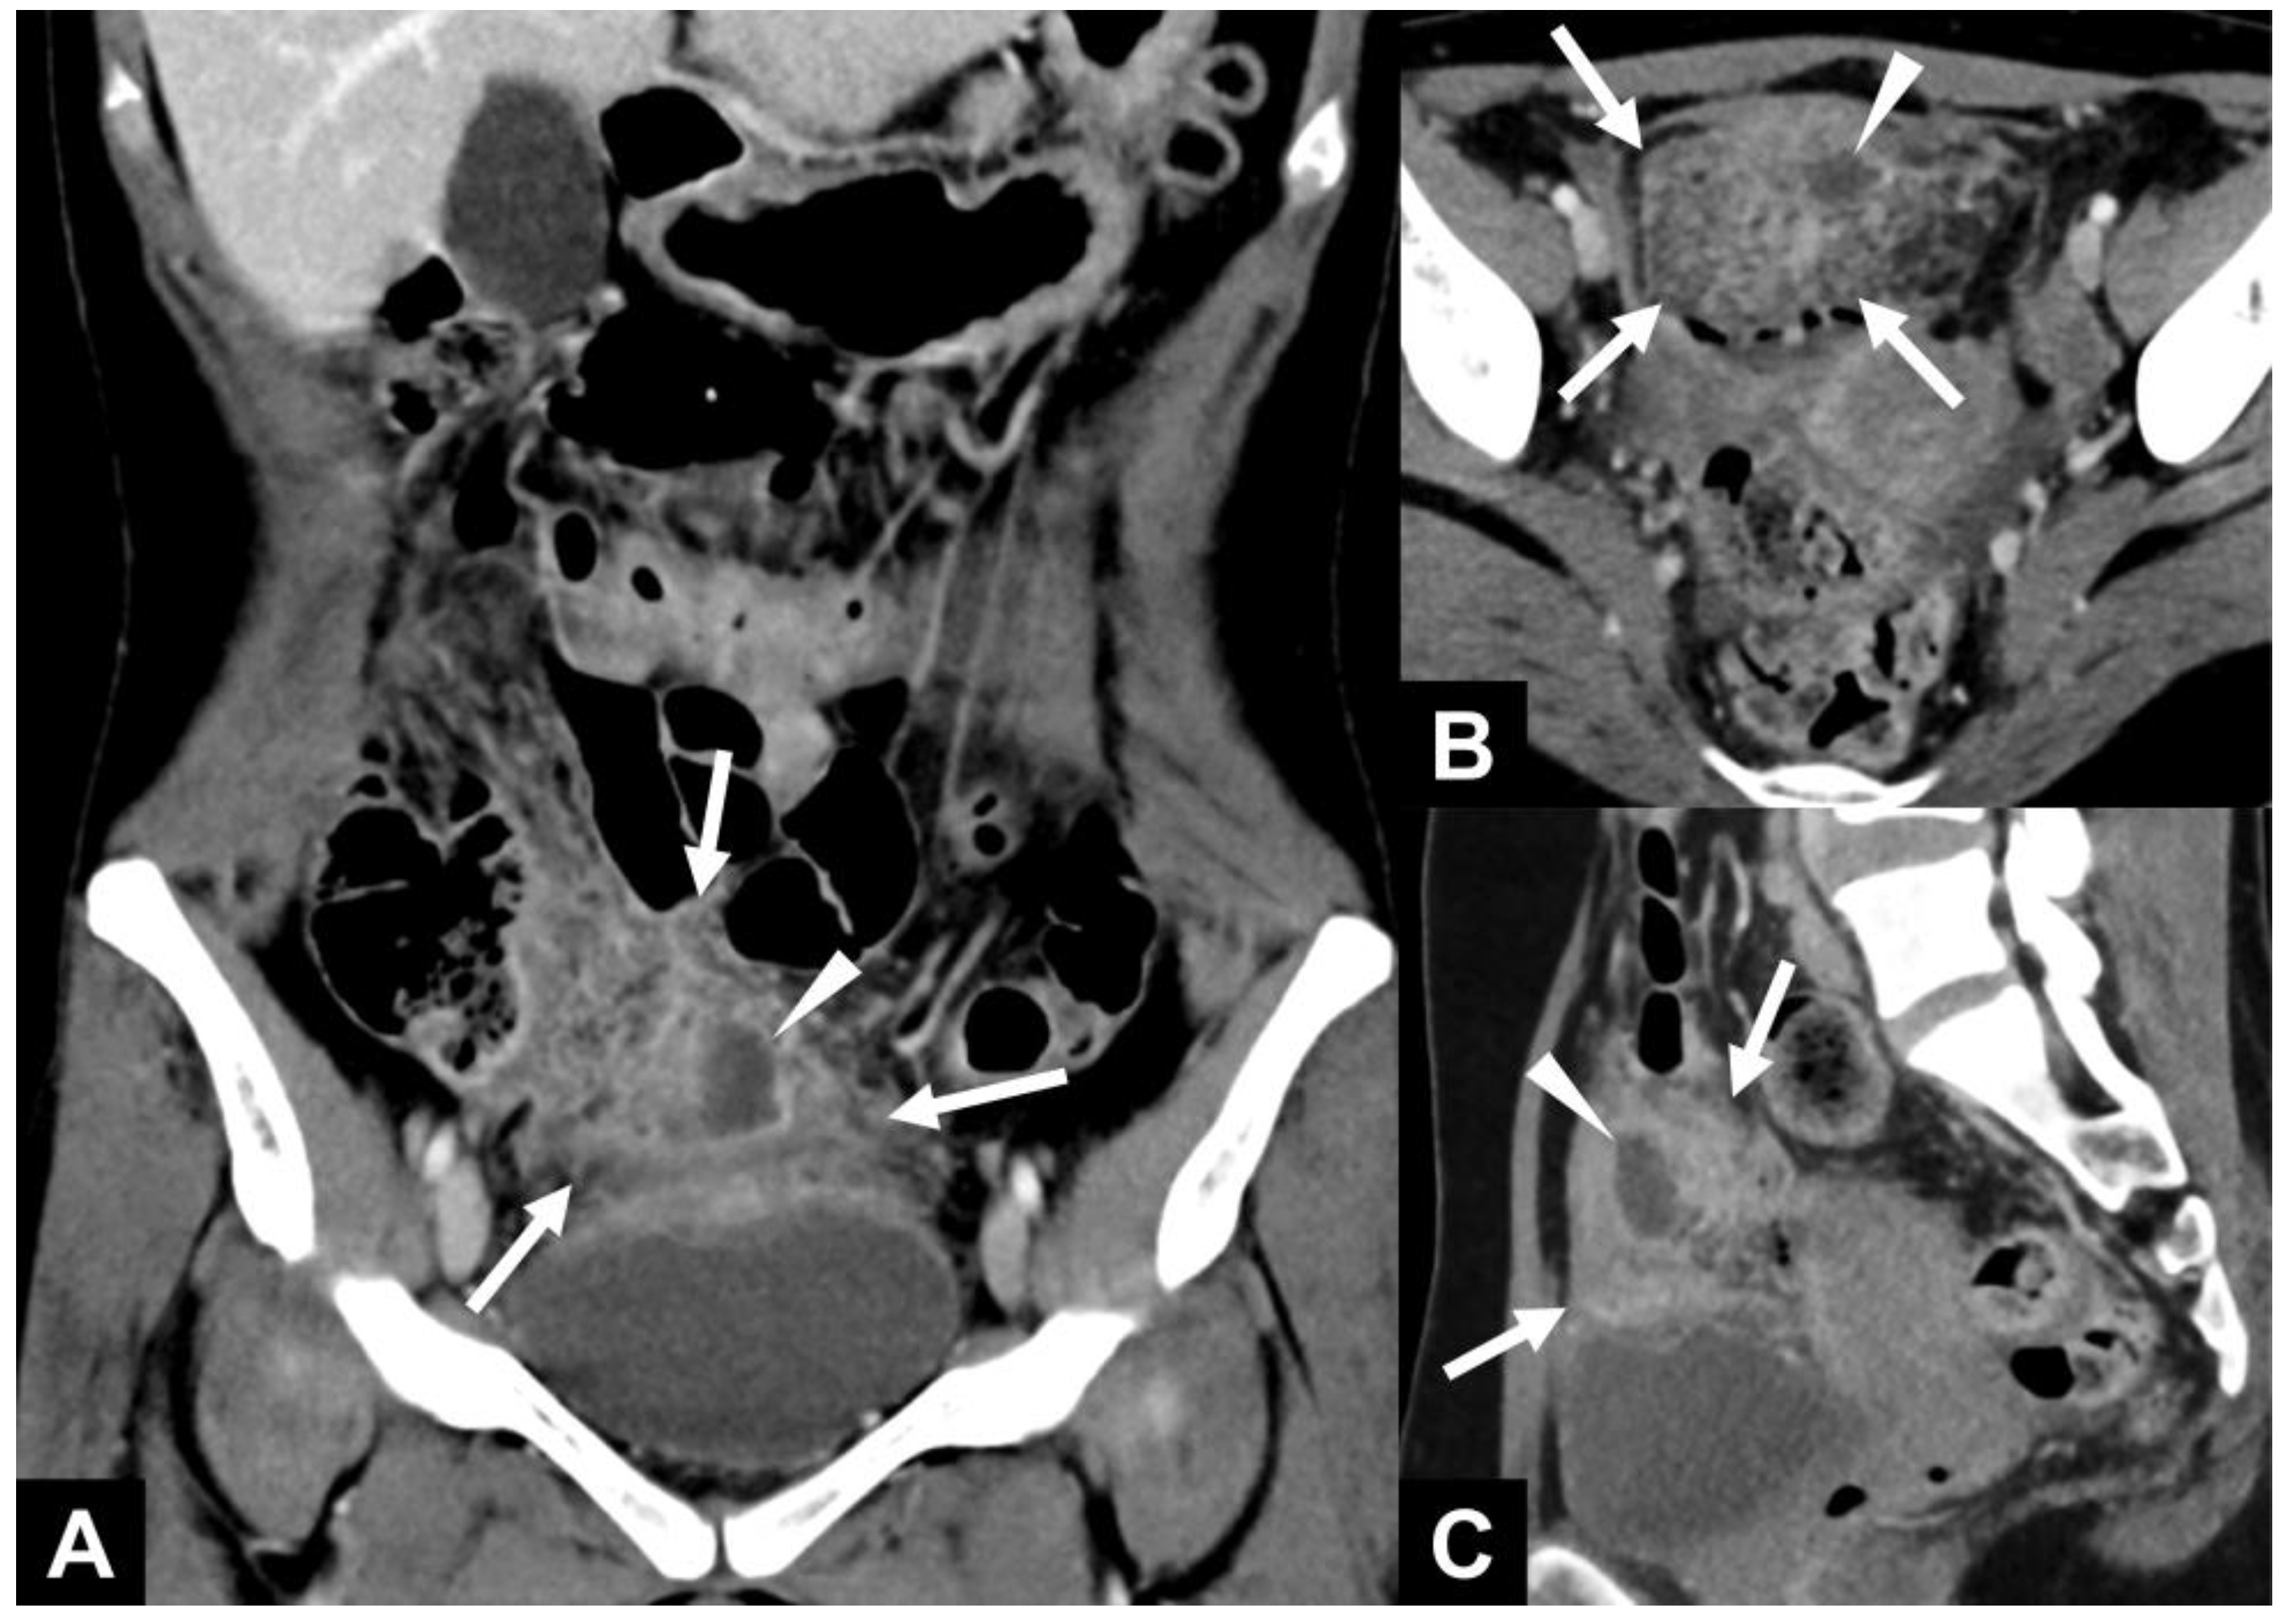

A 41-year-old female patient with no surgical history presented with pelvic pain after the removal of an intrauterine device 4 days ago, without fever and with an increased CRP level (188 mg/L). Clinical examination revealed pain provoked by a vaginal exam, and endovaginal ultrasonography revealed only a small amount of pelvic effusion while the ovaries and fallopian tubes were considered normal. Because of the significant inflammatory syndrome, it was decided to perform an abomino-pelvic CT. Conventional CT (SOMATOM® Definition Edge, Siemens Healthineers, Erlangen, Germany) was performed after the intravenous injection of an iodinated contrast medium in the portal phase. Abdomino-pelvic CT at the portal phase in coronal (A), axial (B), and sagittal (C) reconstructions revealed enlargement and stranding of the lower part of the greater omentum (white arrows) associated with a developing collection within it (white arrowheads). The upper wall of the bladder showed reactive thickening.